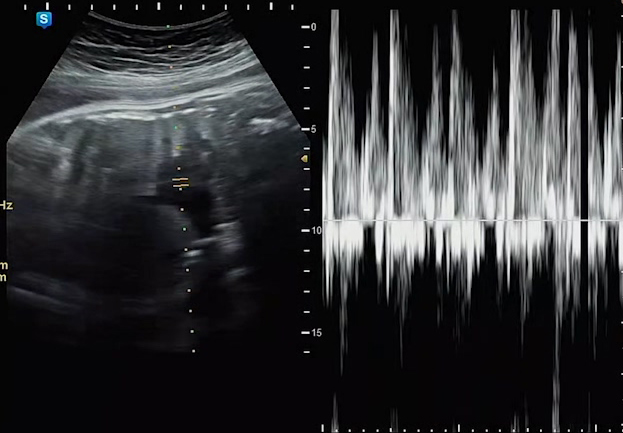

마지막으로 태동검사도 간단하게 했다고 했다. 태동 검사할 때 항상 내가 병원에 따라가지 못했을 때였는데, 이렇게 사진으로나마 볼 수 있게 되어서 신기하기도 했다.

아마 센서 부착된 곳 2군데에서 태아 심장 박동수와 산모의 자궁 수축 정도를 표현해준다. 다행히 결과도 좋다고 하였다. 이제 정말 일주일 가까이 남은 출산일..! 많이 기다려지고, 궁금하고 설레고 복잡한 마음이다.